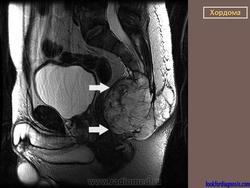

Хордомы могут достигать больших размеров, особенно при их локализации в каудальном отделе позвоночника. Клиническая картина во многом зависит от направления роста хордомы. При росте в спинномозговой канал опухоль вызывает симптомы сдавления спинного мозга, конского хвоста и корешков нервов.

Рентгенологическая картина хордом характеризуется наличием очага деструкции, захватывающего ряд позвонков. Костный дефект представляется однородным, либо крупнокамерным за счет тонких костных полосок. Показаны боковые рентгенограммы крестца, на которых при хордоме определяется увеличение передне-заднего размера крестца за счет экспансивного роста опухоли. В отдельных случаях в опухоли прослеживаются небольшие костные включения, которые могут служить поводом для ошибочной диагностики тератом, особенно в детском возрасте. (В детском возрасте тератомы встречаются часто, их соотношение с хордомами, по данным М. В. Волкова, 60:2).

Лечение хордом - оперативное. В случаях нерадикального хирургического вмешательства могут возникать рецидивы опухоли.

Крестцово-копчиковая хордома.